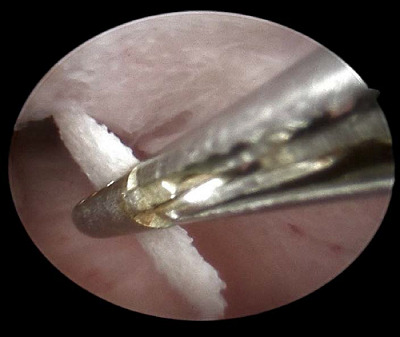

Case presentation: We present two cases of OM presented to the infertility clinic and discuss their similarities and discrepancies in presentation and risk factors. A transvaginal ultrasound raises suspicion about the diagnosis of OM with a hyperechoic mass and post-acoustic shadowing. An office hysteroscopy showed white, mesh-like bony sheets. Both cases underwent operative hysteroscopy to address surgical challenges, and the two cases were followed postoperatively for one year.